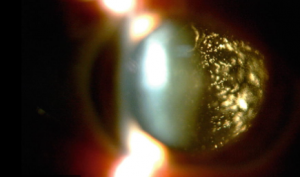

Asteroid Hyalosis

Approximately 1 in every 200 people will be diagnosed with asteroid hyalosis during their lifetime. Most people believe that if they have a problem with... -